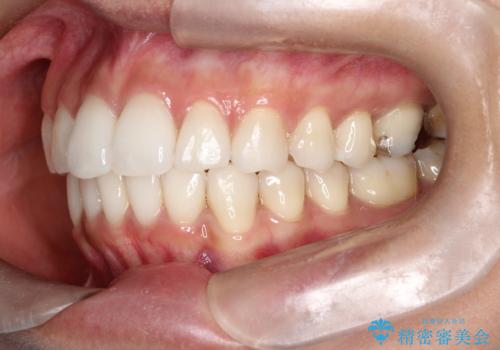

治療では、マウスピースの設計に基づき、奥歯から順に後ろへ移動させる遠心移動を行い、前歯のためのスペースを作りました。同時に、数箇所の歯の間にIPRを施すことで、歯の健康に影響のない範囲で精密に隙間を確保しました。

1年半の治療期間を経て、重なり合っていた前歯はスムーズに整列し、理想的なアーチ状の歯並びへと改善されました。抜歯を行わずに治療を完了したことで、噛み合わせのバランスを維持しながら、審美性を大きく向上させることができました。現在は保定期間に入り、美しい状態を維持されています。